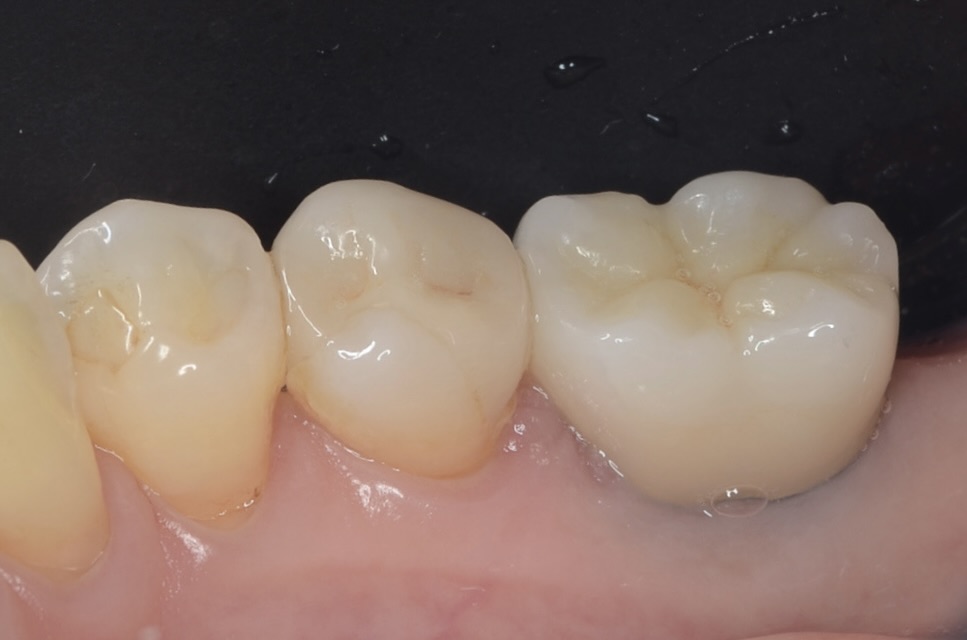

術後6ヶ月

歯肉は安定しました。ここから印象します。 -

ジルコニアクラウン

綺麗に補綴できました。 -